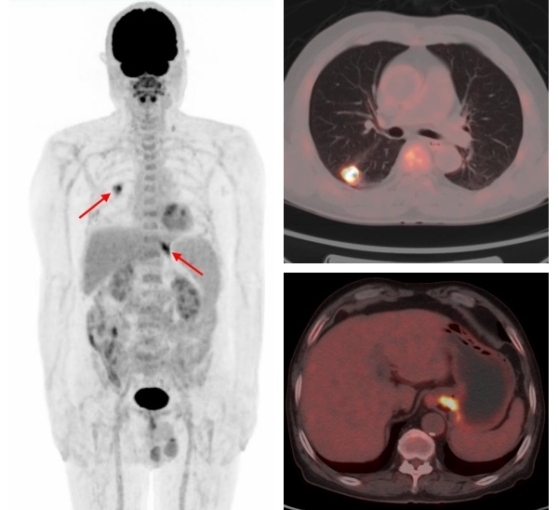

國際頂級腫瘤期刊《美國醫學會雜志腫瘤學(JAMA Oncology)》的數據顯示,65歲以上的老年癌癥患者二次患癌的概率為25.2% 。多原發癌好發于消化系統、呼吸系統和泌尿系統。有研究發現FDG PET/CT在3%的非小細胞肺癌患者中發現了第二原發性惡性腫瘤或癌前病變,從而改變了27%的患者的治療方案。

原發肺腺癌合并賁門腺癌

原發肺鱗癌合并直腸腺癌